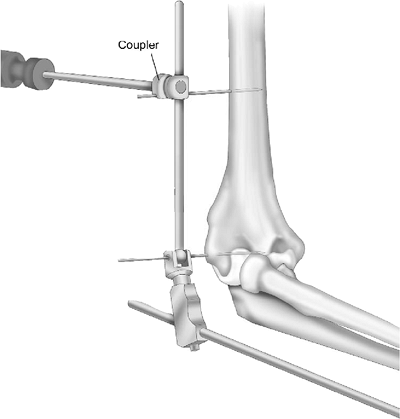

Reference pin removal. The 3-mm Apex humeral reference pin is then removed (Fig. 8-12).

Figure 8-12. A,B: The reference (axis) pin is removed, leaving no interarticular fixative device.